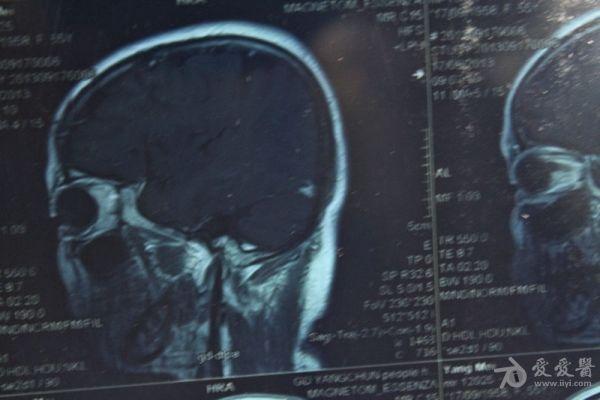

脑部占位病变CT,MRI图片,请帮忙诊断

最近感图样,无其它脑病病史

考虑脑膜瘤!!

磁共振没有平扫,增强矢状位没找到病灶。像脑膜瘤。

图片不是很清楚,应该是脑膜瘤!